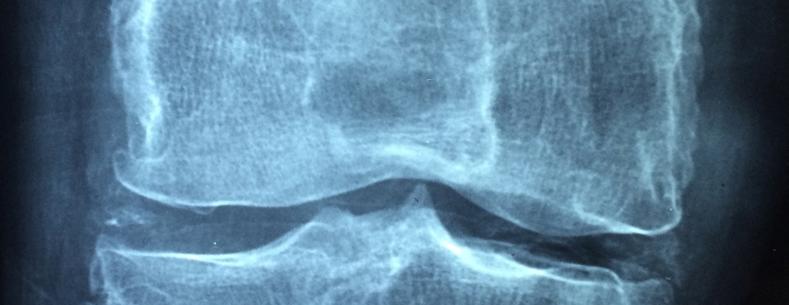

Osteoarthritis yw'r math mwyaf cyffredin o arthritis. Mae'n aml yn cael ei ystyried fel 'traul' ar y cymalau, ac mae'n effeithio ar bobl wrth iddynt fynd yn hŷn. Serch hynny mae hefyd yn gyffredin ymysg pobl o oedran gweithio. Mae triniaeth yn cynnwys meddyginiaeth ar gyfer poen, mesurau ffordd o fyw (ee rheoli pwysau ac ymarfer corff), ac mewn achosion difrifol llawdriniaeth i osod cymalau newydd. Mae'r